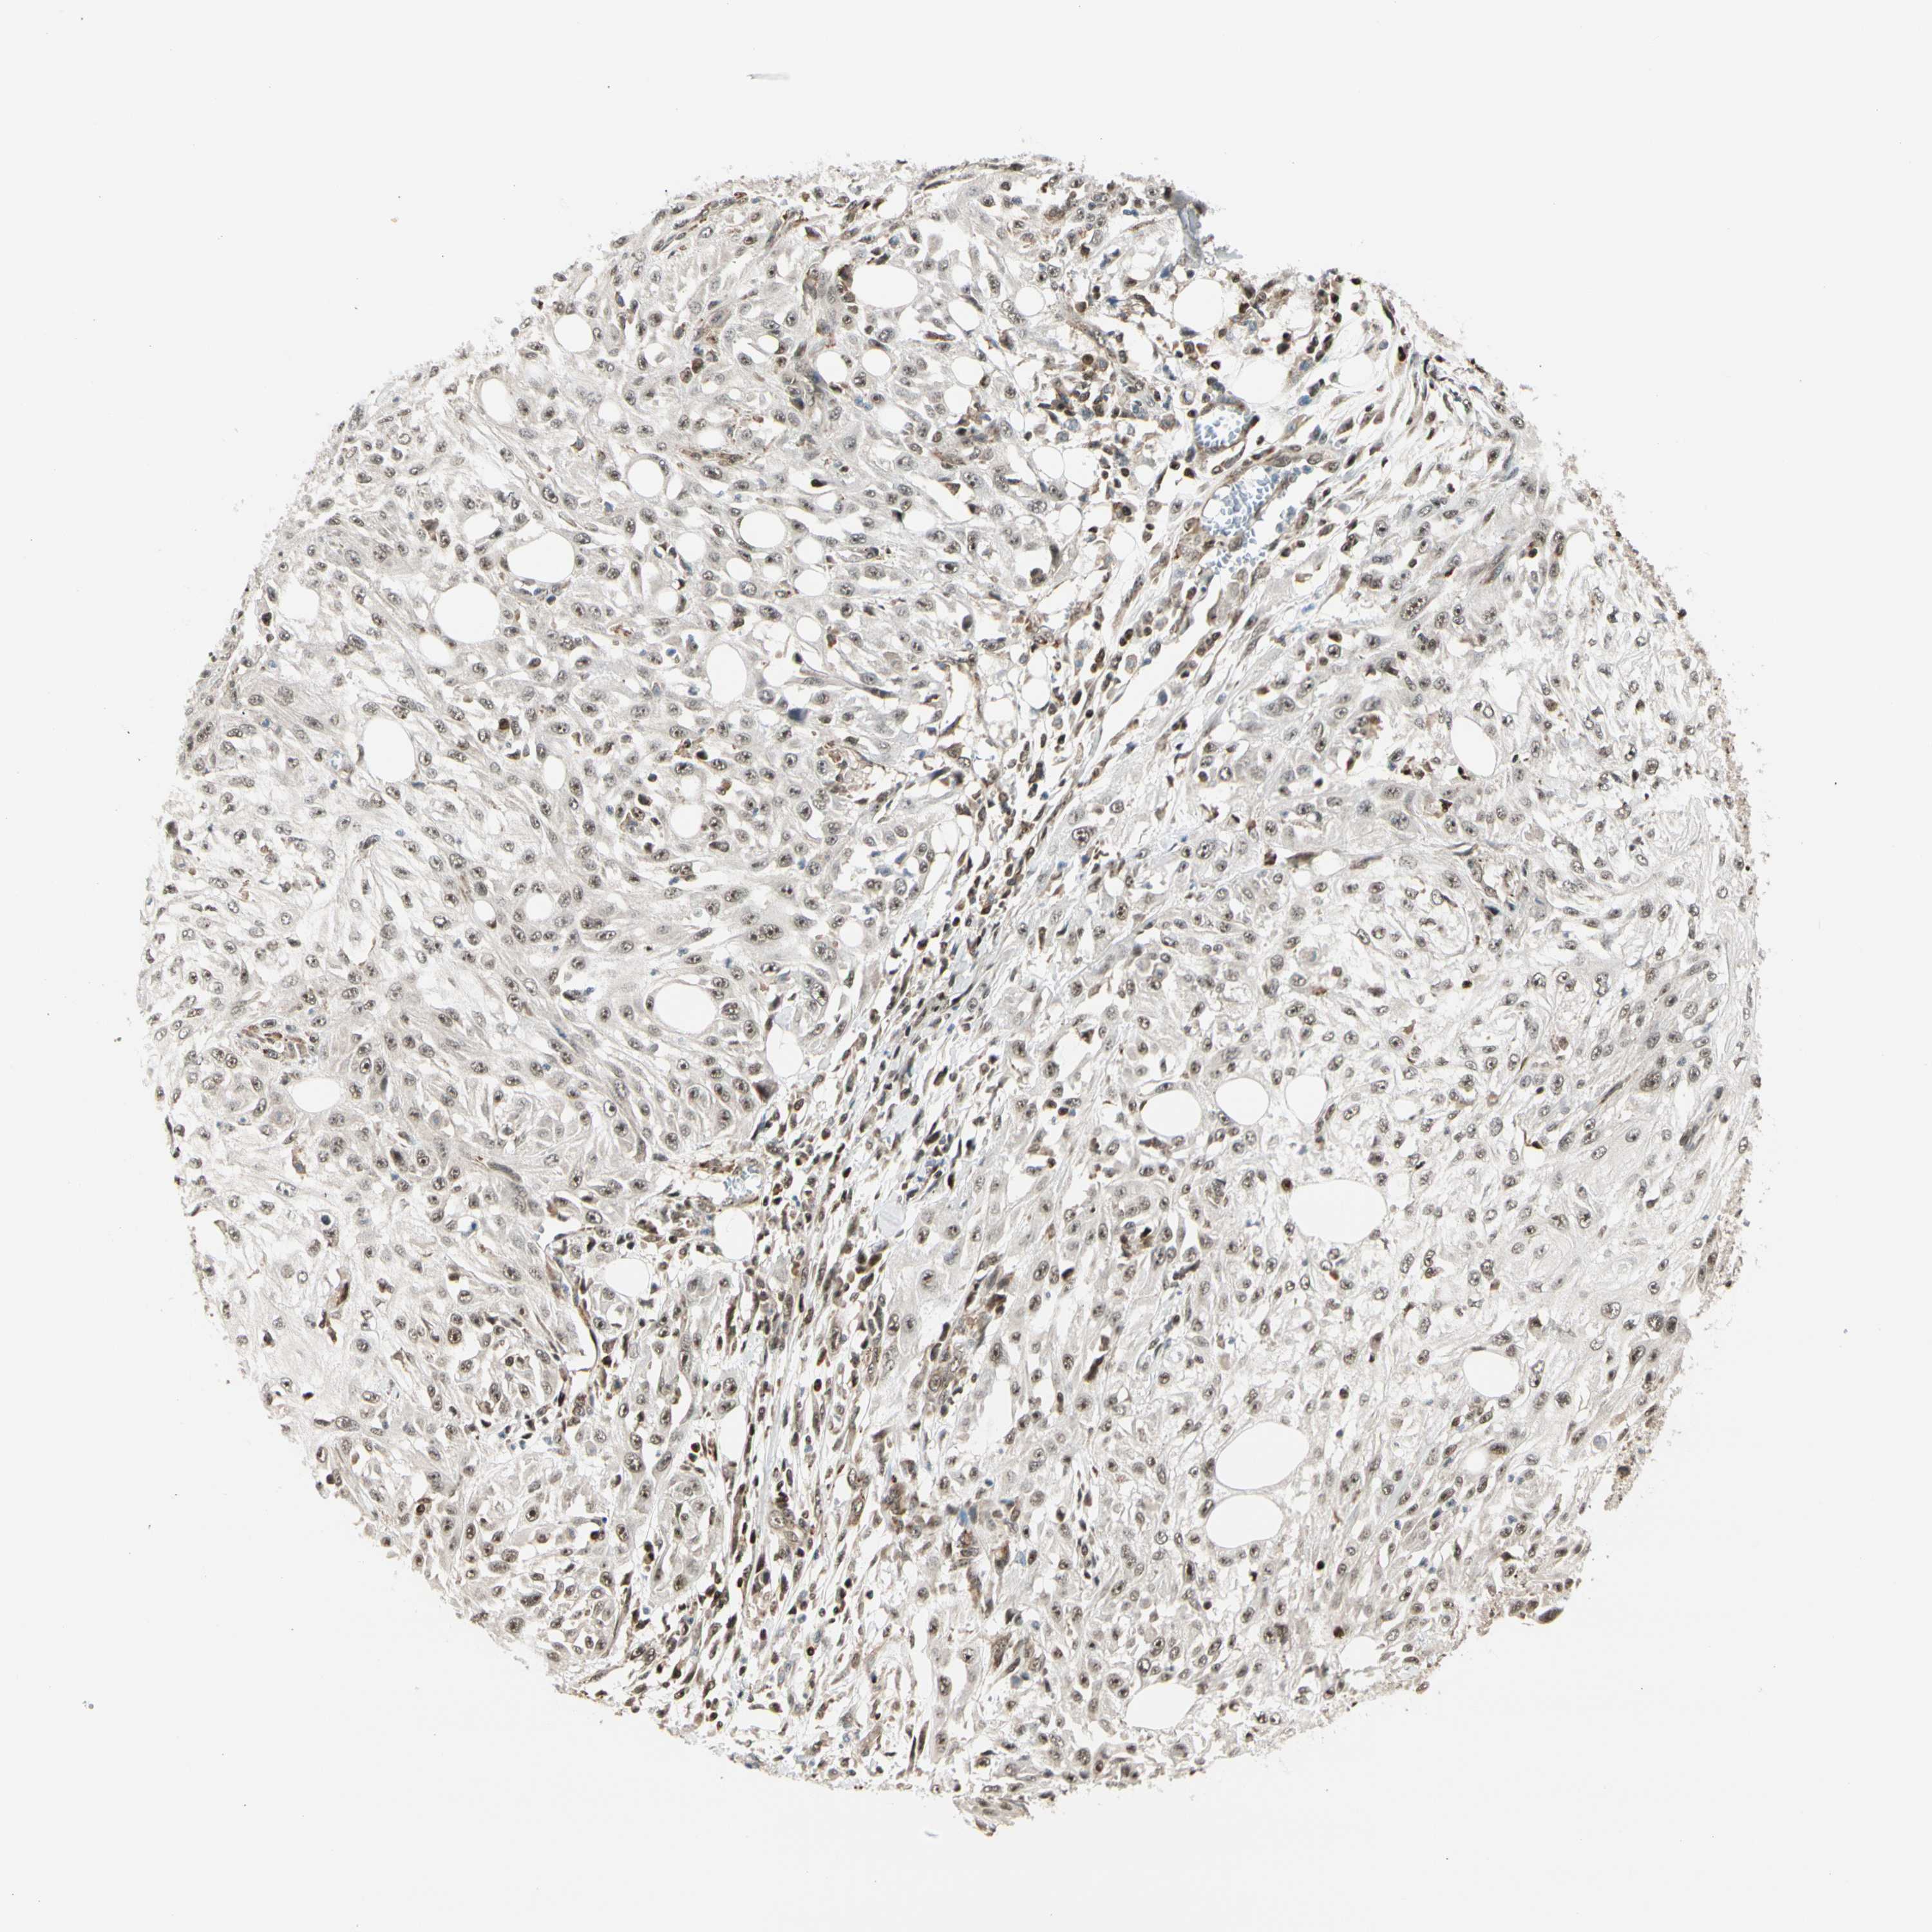

SKIN CANCER - Protein expressioni

A mouse-over function shows sample information and annotation data. Click on an image to view it in a full screen mode. Samples can be filtered based on level of antibody staining by selecting one or several of the following categories: high, medium, low and not detected. The assay and annotation is described here.

Antibody stainingi

Antibody staining in the annotated cell types in the current human tissue is reported as not detected, low, medium, or high, based on conventional immunohistochemistry profiling in selected tissues. This score is based on the combination of the staining intensity and fraction of stained cells.

Each image is clickable and will lead to virtual microscopy that enables deeper exploration of all samples and also displays staining intensity scores, fraction scores and subcellular localization as well as patient and tissue information for each sample.

Antibody HPA008736

Staining

High

Medium

Low

Not detected

Intensity

Strong

Moderate

Weak

Negative

Quantity

>75%

75%-25%

<25%

None

Location

Nuclear

Cytoplasmic/membranous

Cytoplasmic/membranous,nuclear

Squamous cell carcinoma, NOS